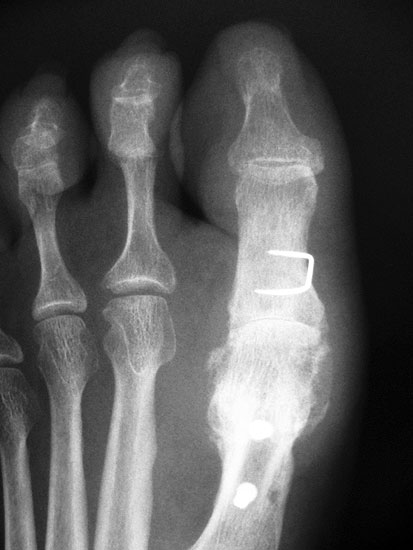

Die dorsoplantaren Röntgenaufnahmen zeigen eine Open-wedge Technik mit der normalerweise ein erhöhter intermetatarsaler Winkel gut zu korrigieren ist (Abbildung 3). Die Wirksamkeit einer Basisosteotomie ist umso größer, je proximaler diese durchgeführt wird. Je weiter distal die Osteotomie, umso geringer die Korrektur. Auf den postoperativen Bildern ist der distal unverändert große Abstand zwischen Metatarsale I und Metatarsale II erkennbar, bei gleichzeitiger Subluxation des Großzehengrundgelenks und dezentrierten Sesambeinen. Darüber hinaus finden sich initiale degenerative Veränderungen im Großzehengrundgelenk. Klinisch bestand eine hohe Weichteilspannung, bei verkürzter Extensor- und Flexor hallucis longus Sehne.  Daher wurde ein verkürzendes Verfahren zur Revision gewählt (Abbildung 4). Die Lapidusarthrodese stellt ein sehr zuverlässiges Verfahren zur Behandlung von Hallux valgus Rezidiven dar 9. Die Fusion des Tarsometatarsale-I-Gelenks kombiniert Stabilität mit einem hohen Korrekturpotenzial. Aufgrund der verfahrensimmanenten Verkürzung des ersten Strahls und der in diesem Fall bereits präoperativ vorhandenen Transfermetatarsalgie wurde die Entscheidung für eine verkürzte Weil-Osteotomie am zweiten bis fünften Strahl gefällt. Die Kombination beider Verfahren führte zu einem homogenen Metatarsale-Index und zu einer gleichmäßigen plantaren Druckverteilung 10. Die Hallux valgus interphalangeus Fehlstellung wurde mit einer Akin-Osteotomie korrigiert.